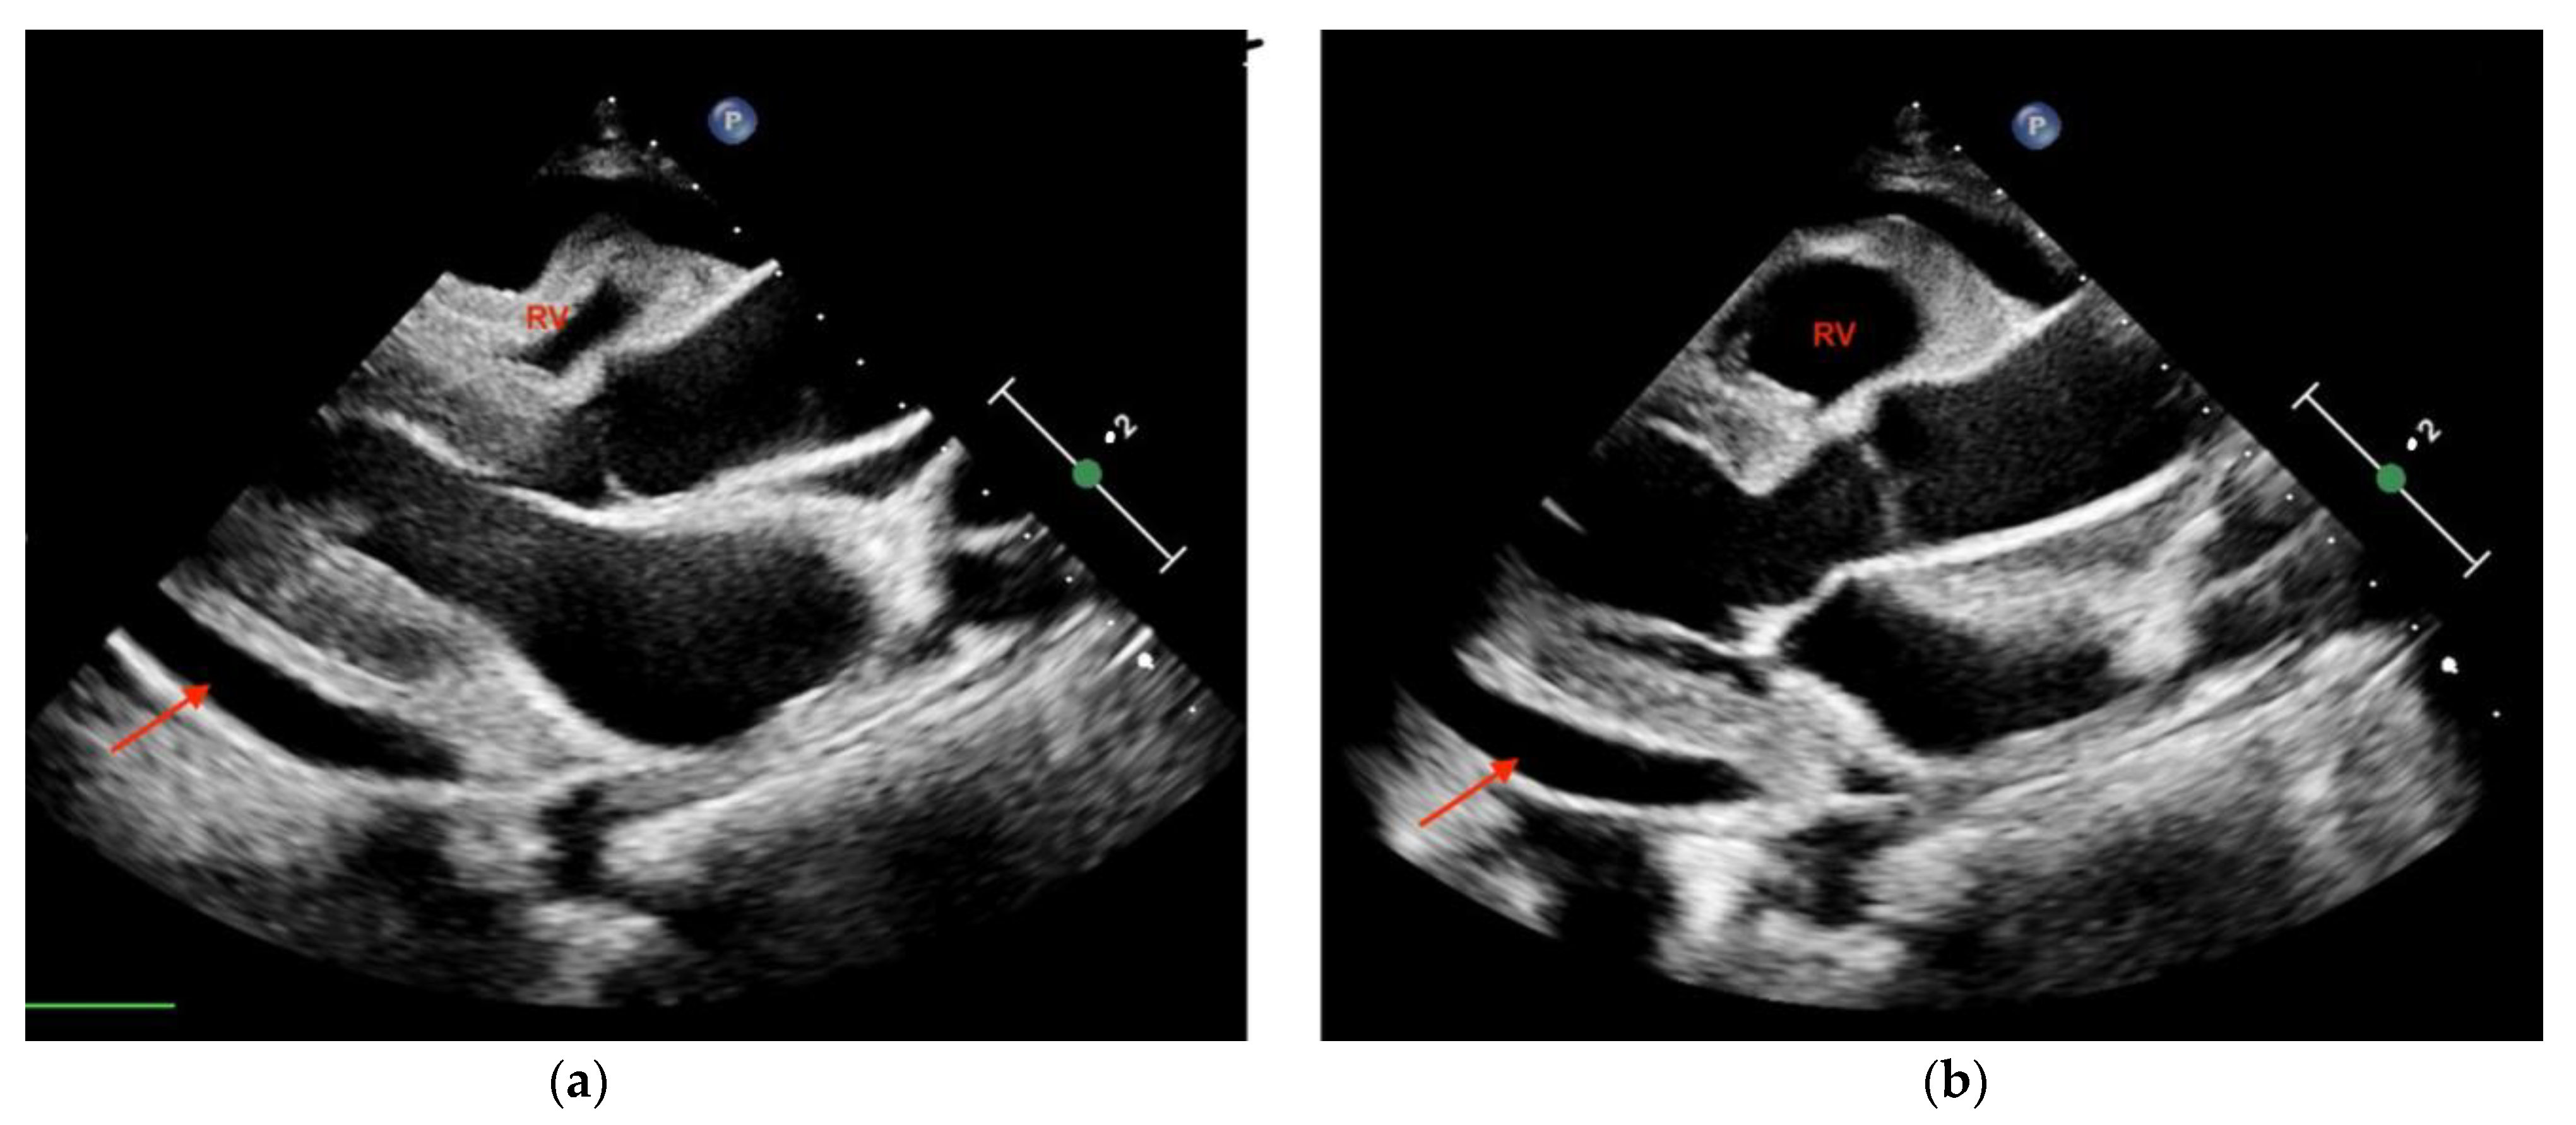

The use of sonography can help diagnose tamponade within minutes. Signs consistent with tamponade include the presence of fluid between the fibrous and serous pericardium, the collapse of the right cardiac chambers during diastole, and a small ventricular size (Figure 2; Figure 3). An exaggerated drop in systolic blood pressure due to impaired filling of the heart might also be identified with a paradoxical shift of the septum during inspiration. A dilated and poorly collapsible inferior vena cava may be observed as well [26]. Prompt intervention for tamponade can quickly address pulseless electrical activity (PEA), leading to higher survival rates compared to other causes of PEA (15% vs. 1.3%) [5,24]. In the presence of suspected or confirmed cardiac tamponade, an emergency pericardiocentesis to drain the accumulated fluid is indicated to restore circulation. The use of sonography also guides and assists with pericardiocentesis, thus enhancing the precision and safety of the procedure, with a success rate >90%. In a study evaluating the use of TTE in patients with cardiac arrest related to trauma, its utilization led to reduced time spent in the resuscitation area. Additionally, a decrease in the necessity for blood transfusions and a reduced need for invasive procedures was shown in these patients, which translated into a lower utilization of resources [27].

Figure 2.

Transthoracic echocardiography (PSLA view) showing the anechoic separation of the pericardial layers measuring 1.4 cm in diastole (arrow). (a) Right ventricle (RV) systolic collapse is shown on the left image; (b) right ventricular outflow tract diastolic collapse can be seen on the right image.

Figure 3.

Parasternal long-axis view of a pericardial effusion as indicated by the arrow. The right ventricle (RV) is not collapsed; tamponade is not diagnosed.